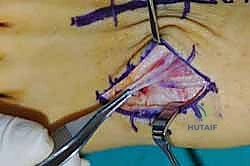

2. الشق الجراحي والوصول للمفاصل

يتم عمل شق جراحي واحد أو شقين (أحدهما في الجزء العلوي الداخلي والآخر في الجزء الخارجي) للوصول إلى مفاصل منتصف القدم دون الإضرار بالأوتار الحيوية والأعصاب والأوعية الدموية. يتم استخدام تقنيات الجراحة الدقيقة (Microsurgery) للحفاظ على الأنسجة المحيطة السليمة.

3. إزالة الغضاريف التالفة (Joint Preparation)

هذه هي الخطوة الأهم. يقوم الجراح بكحت وإزالة جميع الغضاريف المريضة والتالفة من بين العظام المراد دمجها. يجب الوصول إلى العظم الإسفنجي الصحي (Cancellous bone) الذي ينزف دماً، لأن هذا الدم يحتوي على الخلايا الجذعية وعوامل النمو الضرورية لعملية الالتحام (Fusion).